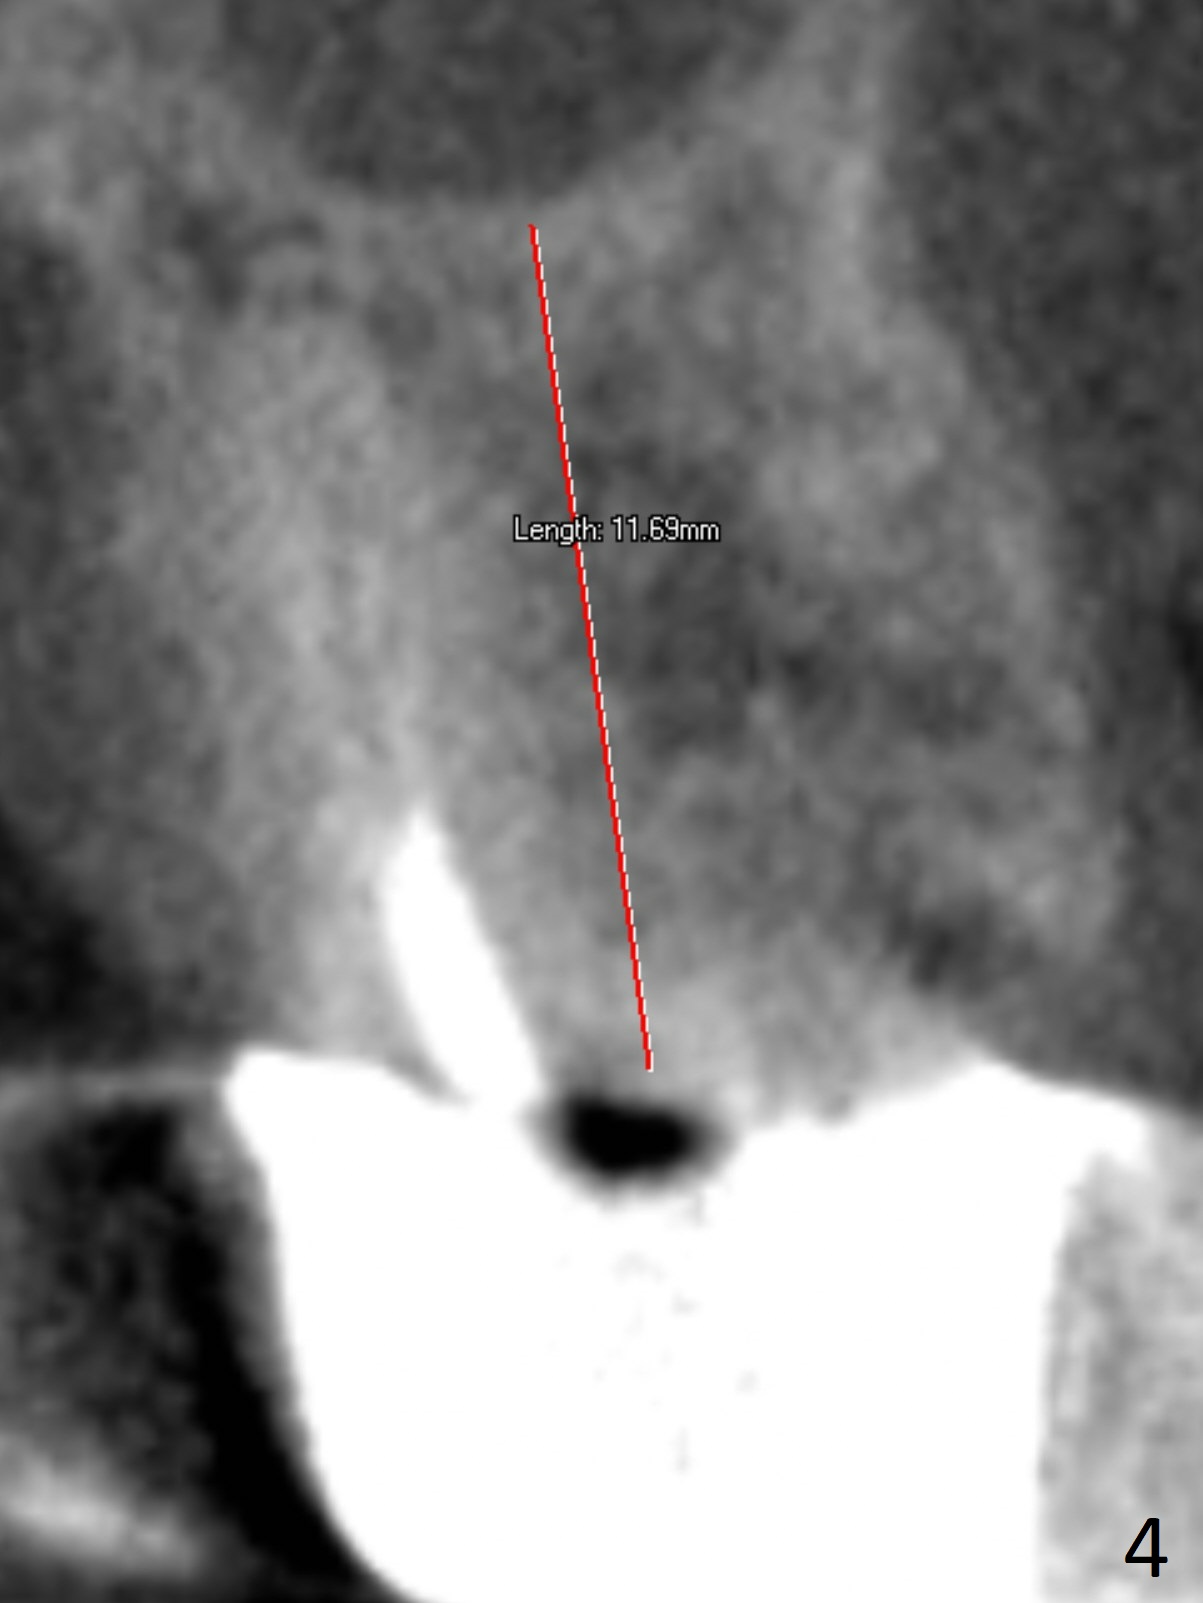

A 70-year-old woman fractures the crown at #14 (Fig.1). A 5x11 mm implant will be placed at the septum (Fig.2). Osteotomy depth can be determined using bony (Fig.3 with stopper) or gingival (Fig.4,5 with vision) landmark. The CT was taken 5 years earlier. Sagittal (Fig.6) and axial (Fig.7) sections confirm suitability of the 5x11 mm implant for the site. Prepare surgical handpiece for sectioning the tooth for extraction. After drills, use Magic Expanders for sinus lift. Place Vanilla Graft prior to dummy implant(s). A bone-level implant crown may be easier to be repaired if the proximal contact is not ideal.